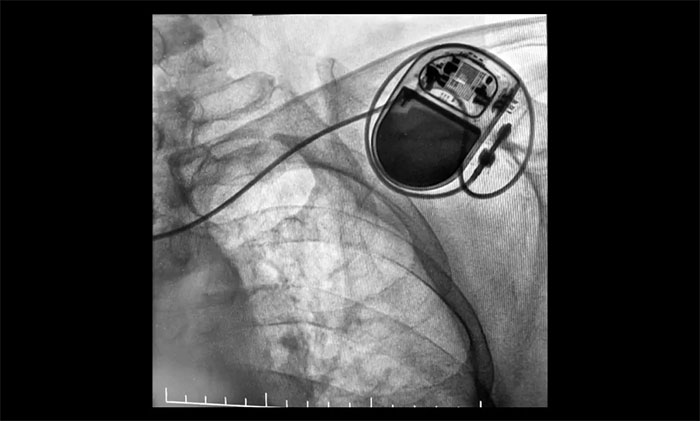

包括心脏电复律(用于房颤、室速等紧急情况)、射频消融术(适用于房颤、室上速的治疗)、植入心脏起搏器(适用于严重心动过缓)或埋藏式心脏除颤器(ICD)(针对高猝死风险者)。

▲ 心脏起搏器顺利植入

近日,上海蓝十字脑科医院成功完成首例永久性心脏起搏器植入手术。该患者为老年女性,因阵发性房颤伴显著房性心律失常及窦房结功能不良,存在心跳骤停高风险。手术在DSA引导下耗时40分钟顺利完成,出血不足5毫升,术后起搏器功能良好,患者正在康复中。